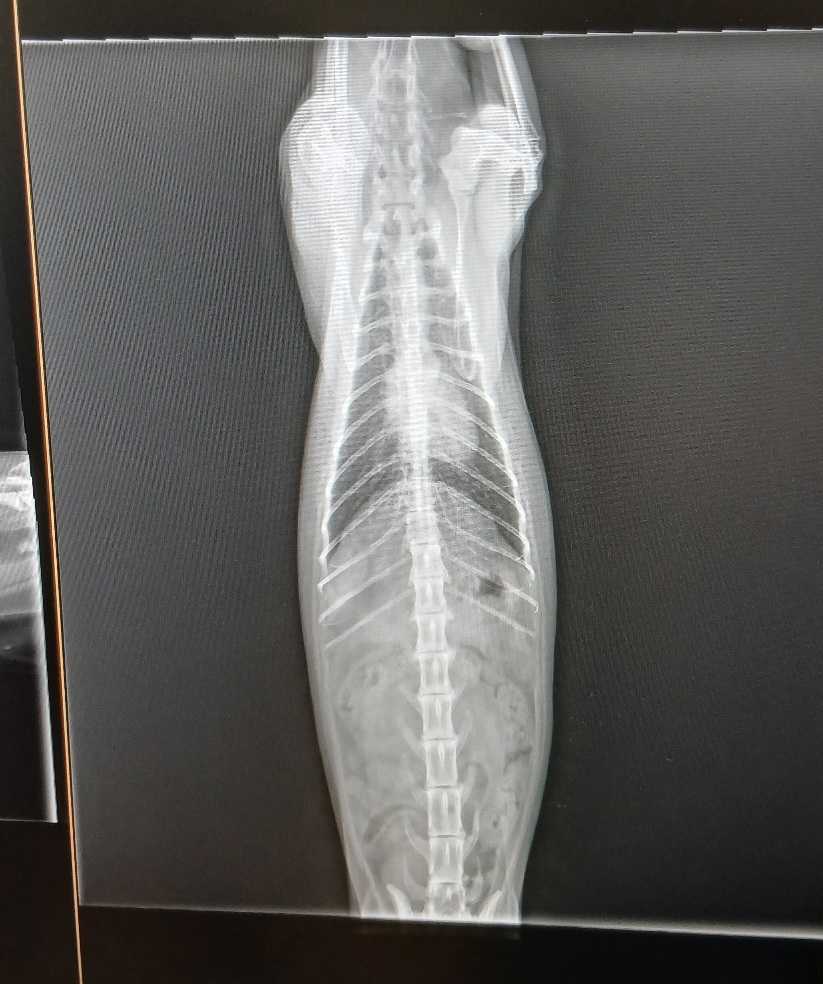

今日は いつものように午前中は動物病院へ。いつもの麦ちゃんと、たーちゃんを連れて。麦ちゃんは腎臓に結石があるが毎週 皮下補液だけでたまにはレントゲンを撮らなくてもいいのだろうか?と聞いたらもし腎臓が腫れていれば触診でわかるから、今のところは必要ないけど、年に一回くらいは検査してもいいかな、とのことでひとまず安心。たーちゃんは今日は迷ったけど連れていった、来週はお彼岸で動けないし。どこがどうというわけでもないというか、ついこの前も診てもらったばかりだけど鼻水と涙がひどく、薬をもらって飲んでるものの、一向によくならない。最近は食欲もいまいちで、あれこれ出してもなかなか食べてくれない。たーちゃんも多分 15歳は超えてる高齢だしなぁ、、と考えたけどそれで諦めずに念のため、念のため、と自分に言い聞かせ何もなければないで、安心を買えていいじゃないか、と思うのだ。「このまえからもらった薬を飲んでいて、一時的に良くなったけど、また状態は変わらなくなってしまった、涙と鼻水と咳。涙は涙管が詰まってるのでともかく、鼻水と咳がねぇ、食欲もない感じで。たーちゃんは血液検査いつやったっけ?半年以上経ってるなら、腎臓数値も悪化していないか確認したい、食べてないから皮下補液もしたいけど、まぁそれは家でもできるかな、必要があればレントゲンも」私は基本 何をしてほしいかをある程度伝えるようにしている。必要がなければ却下されるし、必要があればやってくれる。血液検査は2月にしたというので、今日はしてもらった。ヒトの1ヶ月は、ネコの4ヶ月に相当するから、半年以上経ってるならやった方がいいかなって思って。たーちゃんの実年齢は不祥だが私がここに越してきた2012年に、最初にTNRした子なので、あの時2~3歳だとしても、15歳にはなっているはずだ。毛並みの感じとか、爪の太さとか見ても、最近はホントにおじいちゃんぽくて心配になる。もしかしたら、17~8歳の可能性も充分ある。基本 高齢の子にあれこれ過度な医療をかけるつもりは毛頭ないけど不安は払拭したいし、現状を知っておきたいとは思ってる。検査の結果は血液検査は前回と変わらずBUNが若干高いまま、悪化はしていない。レントゲンの結果も気管支や肺に異常があるわけでもなくきれい。心臓も大丈夫、問題なし、とのこと。ただちょっと、関節炎で脚が痛いかなぁ、、と、先生は言っていたけど、それも前回と同じ。特段 何もなく よかった。なんとなく元気がないのはやはりよる年波ということかこの頃は、フータが元気で救われる。つい最近まで どんよりしていて動きもスローで心配だったけど最近は安心して見ていられるのだ。ご飯もよく食べ 時折走り回っている。フータは本当にすごいな愛ちゃんも元気で助かる。最近はまた少しだけ起きている時間が増えた。この前まで、ひたすら眠り、ご飯を食べたらまたすぐ眠り、、だったのが食後も少し起きているし、なんならケージから出てくることも増えた。愛ちゃんがケージからのしのし出てくるとお、元気だね!と思う。しかし皮膚炎の臭いは変わらずで皮膚炎が起きてるわけでもないのだけど、皮膚炎がこれから起きるであろうあの臭い、、なんだろな、生臭い感じの。拭けば身体は汚れているし愛ちゃんが歩いた後は皮脂汚れのようなものが床にたくさん落ちる。愛ちゃんが我慢できる限界のところまでは 私も頑張って拭いたりするけどすぐ怒り出すからなかなか捗らない。ブラシがイチバンいいだろうけどなぁ 無理だしなぁホント薬湯にでも入れたいくらいだ。愛ちゃんは体を拭かれて我慢ならなくて、ブシャーブシャーと怒るだけでは収まらず、ギリギリと、歯軋りまで始める。ギリギリ歯を鳴らしながら 自分の体にまで噛みつくのでそうなると手に負えないからもうそれ以上は絶対ムリ。ごめんごめんとなだめて 抱き上げてベッドに戻す。しばらくはベッドに八つ当たりして怒りが収まらないけど、しばらくするとまたコテンと眠る。愛ちゃんのベッドに敷いてるタオルは毎日取り替えて洗濯するけど、本当に驚くほど汚れている。自分で毛繕いできないうえに、膿皮症なんだろうな、、と思ってる。ブラっシングが好きな子ならなんとかなったのにねぇ、、ミケ子はあれから私の知る限りでは痙攣発作は起きていない。今日先生に話したら、てんかんノートをくれた。これに、発作が起きたときの状況や時間を記入して、って。例えば 雷のときに発作が起きた、とか明け方、とか、夜中、とか。その頻度で投薬を考えましょうって。しかしやはり、不在時に起きていたらそれはわからないんだよね、、けろっとしちゃうから。てんかんのコントロールもなかなか難しいと思う。CBD オイルでなんとか軽減するといいなと願うばかり。さーて 明日はなんと週末なのにひとりシフトですよ仕入れも多いっちゅーのにしかし予報は雨最近の売れなさを見る限り 大丈夫過ぎるほど大丈夫な気がする…仕入れの日はやること多いんだけどねがんばりまっしょいもう寝なければ、また2時を回ってしまったぐんない